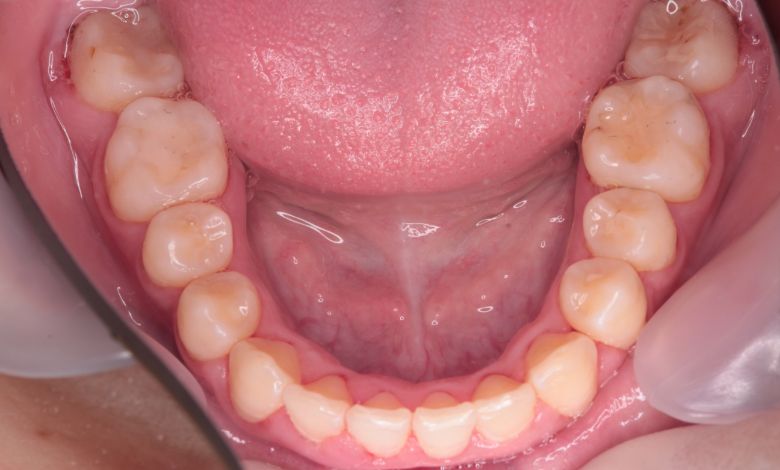

前歯が綺麗に揃っている

下顎の歯列では、前歯部に強い重なりが見られ、中切歯および側切歯がねじれたり前後にずれて生えているのが確認できる

術前に認められた前歯3本の強い重なりは完全に解消され、スムーズな歯列が形成されました。

精密検査の結果、抜歯を行わずに歯列弓を拡大する治療方針を選択。歯が正しい位置に並ぶスペースを

確保したことで、歯列は自然なU字型に整い、叢生が解消されました。見た目の改善だけでなく、

咀嚼機能の向上や清掃性の改善といった機能面での効果も期待できます。